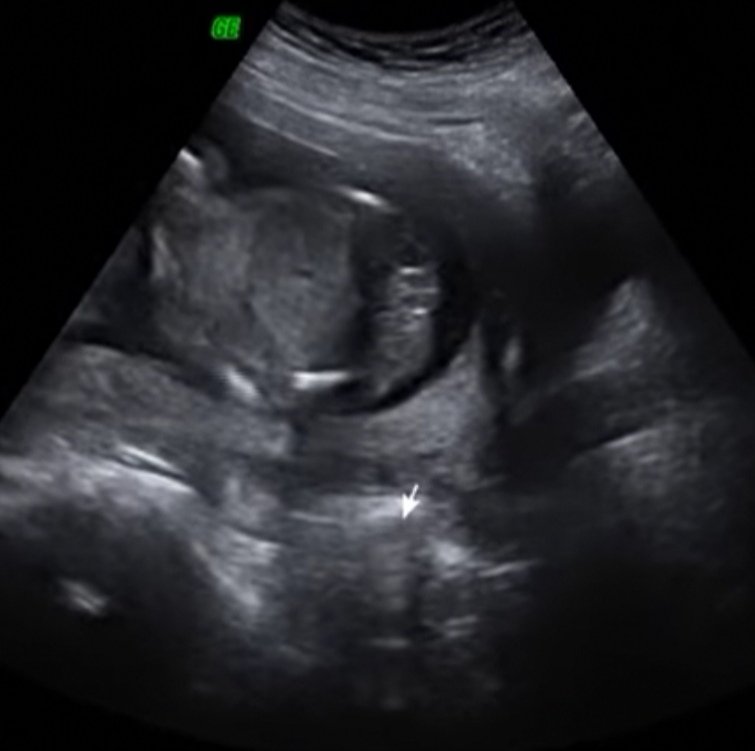

Dziewczyny mała zagadka. Jaka to płeć?